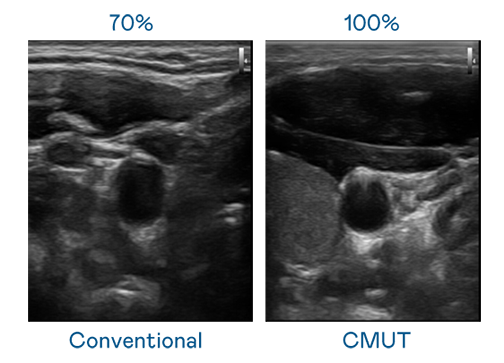

CMUT 技术是一种用电容式微机电元件来产生超音波讯号的技术。与传统 PZT 压电式技术相比,CMUT 频宽增加 30%,更宽频的超音波讯号让影像解析度大幅提升,是实现高影像品质医疗超音波扫描、促进精准医疗发展的关键技术。

大频宽带来超清晰影像

超音波影像的解析度高低,首先取决于探头能发出的讯号频宽。大发平台 CMUT 可提供高清晰的超音波讯号,提供高频宽、高灵敏度、影像纹理细节更高的超音波影像,协助医护人员缩短影像判读时间及利用精准的医疗影像进行诊断。